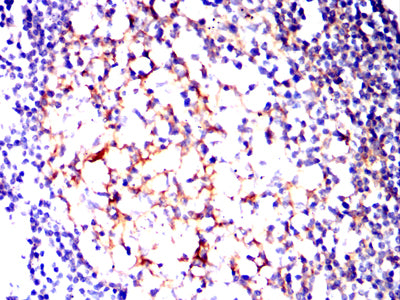

Immunohistochemical analysis of paraffin-embedded human cervical cancer tissues using CD82 mouse mAb with DAB staining.

Immunohistochemical analysis of paraffin-embedded human lymph tissues using CD82 mouse mAb with DAB staining.